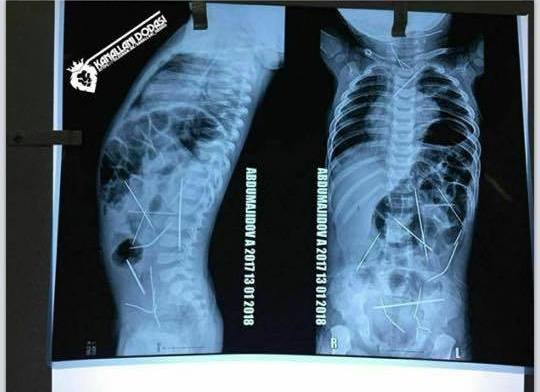

Узбекские врачи продолжают бороться за жизнь 11-месячного малыша, в теле которого обнаружили 16 иголок, сообщает NUZ.UZ.

По словам директора Республиканского научного центра экстренной медпомощи Асилбека Худаярова, состояние мальчика оценивается как крайне тяжелое. "Операция была очень сложная. Ребенок несколько часов провел под наркозом. Кроме того, он несколько месяцев жил с инородными телами, которые, естественно, не были стерильными. Все это время организм как мог боролся, поэтому у пациента была диагностирована выраженная интоксикация. Да, пока проведена только одна операция. Несколько игл все еще остаются в теле мальчика.

Я постараюсь объяснить: в медицинской практике есть два понятия - абсолютные показания и относительные показания. То, что врачи извлекли те иглы, которые угрожали жизни пациента, - это абсолютные показания. То, что в теле малыша осталось несколько игл, не угрожающих жизни, мы считаем относительными показаниями. Оставшиеся иголки находятся в таких местах, что во время удаления может возникнуть нарушение целостности какого-то жизненно важного органа. Поэтому пока остановились и оставили в таком состоянии", - прокомментировал представитель больницы.

В настоящее время ведется доследственная проверка и отрабатываются все возможные версии. По предварительным данным, иглы попали в тело ребенка через кожу. Об этом изначально заявил хирург, проводивший сложнейшую операцию.

- 22 января стало известно о том, что врачи в Ташкенте провели сложнейшую операцию по извлечению игл из организма 11-месячного мальчика. Этот случай шокировал общественность. А после заключения медиков о том, что эти иглы не могли попасть в тело ребенка случайно, начали расследование и правоохранительные органы.